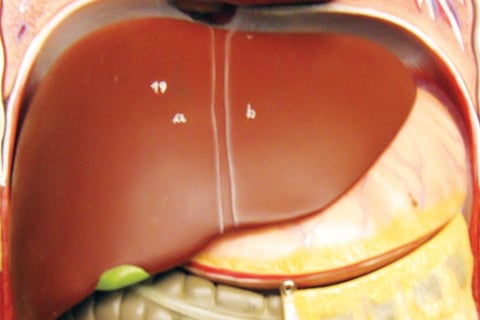

مرض الكبد الدهني، المعروف أيضًا باسم مرض الكبد الدهني غير الكحولي (NAFLD)، يتضمن تراكم الدهون الزائدة في الكبد.

يعاني العديد من الأفراد من أعراض قليلة أو معدومة، على الرغم من أن بعضهم قد يشعر بالتعب أو الانزعاج في الجزء العلوي الأيمن من البطن.

وغالبًا ما يُرى هذا المرض لدى الأشخاص الذين يعانون من زيادة الوزن أو السمنة.

يمكن أن يحدث تلف خطير في الكبد، مما يؤدي إلى حالات مثل التشمع وحتى السرطان.